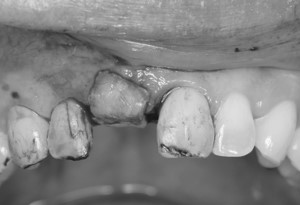

右上前歯にインプラント治療とGBR(骨誘導再生法)を行った症例

こちらの患者様は35歳の女性の方です。

20年程前に右上前歯に外傷の既往があり、その際に神経の治療とかぶせ物の治療を行いました。

今回、同歯が保存困難となり、抜歯後インプラント治療を行いました。抜歯後の骨の欠損が著しかったため、骨誘導再生法(GBR)を併用しました。

歯肉の形を整えるため結合組織移植術も併用しました。 -

仮歯を使用して歯肉の形を整えていきます。

治療後は、歯肉の形も整い笑った際にも天然の歯と変わらない自然な仕上がりになりました。